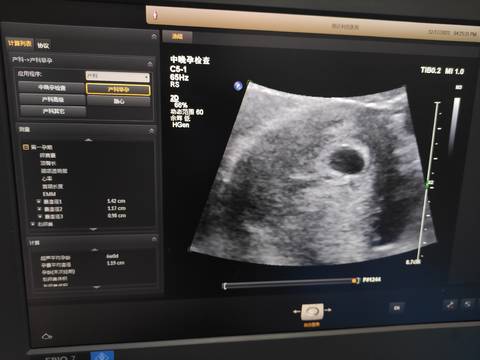

亲爱们。想问一下末次月经10月28号,月经规律。今天五十天后做彩超显示孕囊像6个月大小,还有没有胎心胎芽?正常么?用不用保胎治疗

journal_insert_pic_1681667420